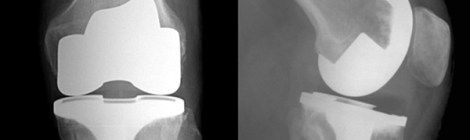

Neuropathic pain post Total Knee replacement

Very interesting Study on Nerve pain following Total Knee replacement.  I have seen a few of these patients over the years and this study reveals that out of 54 patients […]